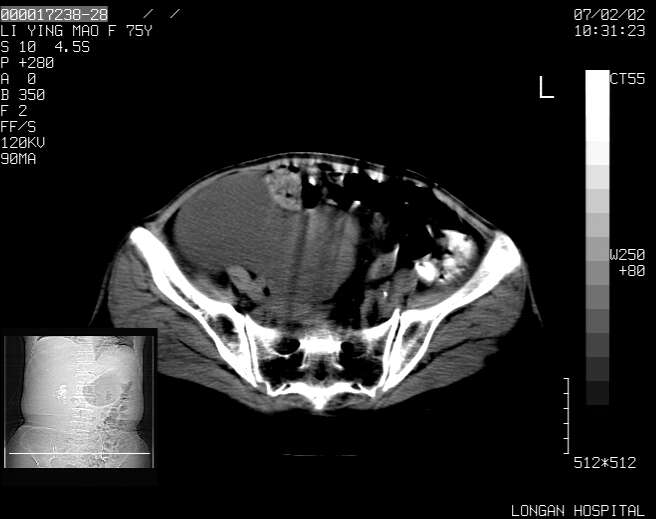

以下是引用dyqct在2007-2-10 8:53:00的发言:[br]考虑:1、肝脏多发囊肿[br] 2、左肾囊肿,右肾多发结石并积水。[br] 3、右胸少量积液。[br] 4、右肾周包裹性积液或淋巴管瘤(有见缝就钻的征象、薄隔、小结节状钙化)?[br] 5、腰椎动脉瘤样骨囊肿?[br] [br] [br]